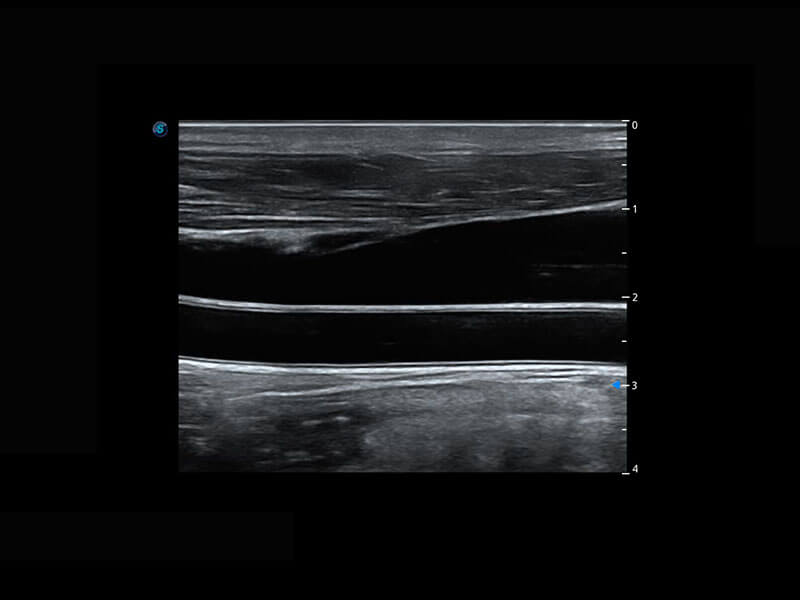

乳腺超声 / 新生儿

P60搭载宽频带线阵探头、宽景成像、弹性成像技术,为您提供乳腺应用方案。P60支持高频相控阵探头、线阵探头、腹部高频探头、腹部微凸探头等,丰富的探头群搭载敏感的彩色血流成像,适用于新生儿多种脏器检测要求,满足新生儿筛查需求。

• 乳腺导管癌

• 乳腺癌显微血流

• 新生儿肝血管癌

• 新生儿脊髓圆锥

• 新生儿心脏